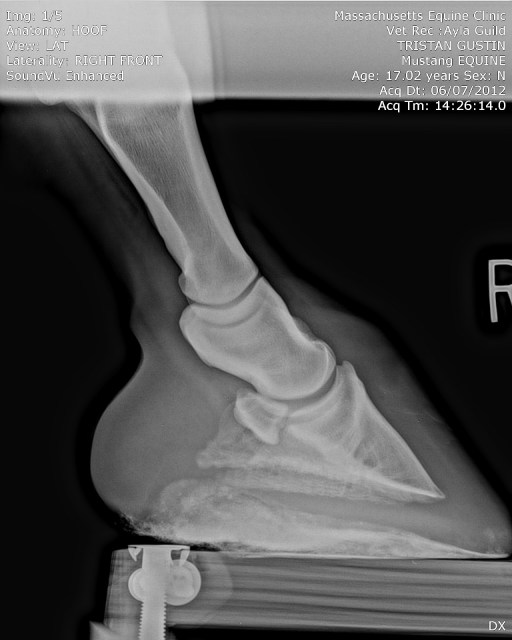

| First, from June 7: clean foot for comparison. |